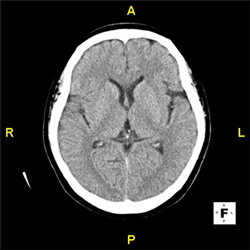

1. 頭部

CT(Computed Tomography)検査は、X線を用いて得たデータをコンピューターで処理し、頭部や身体の輪切りの断層写真を撮影する検査です。

X線の吸収差(CT値)から身体の中の臓器・組織を識別します。